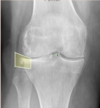

**Answer: Ewing's sarcoma** ## Footnote This image shows a zone of decreased radiodensity in the proximal tibial diaphysis (red overlay) with a lamellated periosteal reaction, seen as the typical onion skin appearance (blue overlay and arrow) of Ewing sarcoma. In Ewing's sarcoma, a (11;22) translocation is characteristic. Biopsy will reveal small, round blue cells that resemble lymphocytes. It can be confused with lymphoma or chronic osteomyelitis, and often presents with metastasis. It is responsive to chemotherapy.